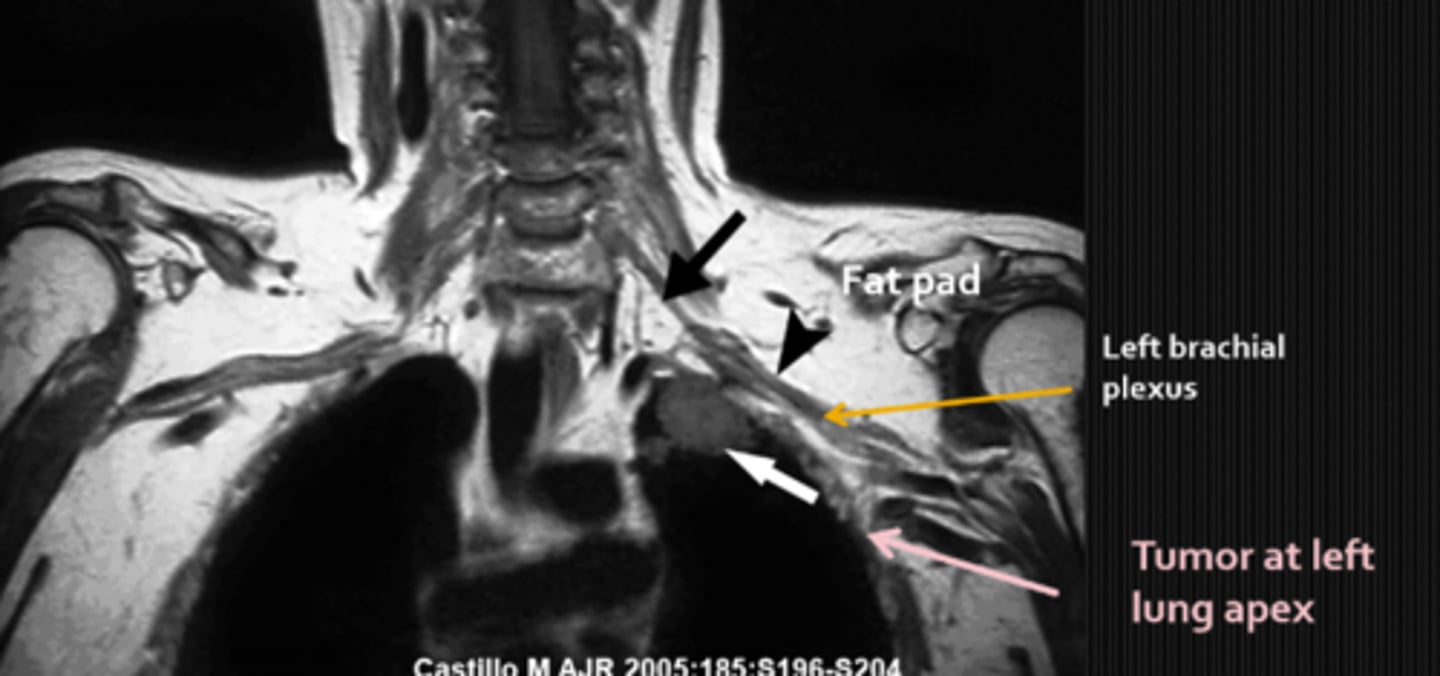

Pancoast tumor that affects the symp fibers traveling over apex of lung

What are some findings of a Pancoast tumor?

Horner's syndrome

chest pain